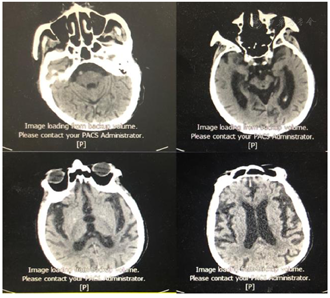

患者医学影像学检查如图1,图2,图3,图4,图5,图6,图7,图8所示,实验室检查结果如图9,图10,图11所示。

患者外伤后左侧股骨颈骨折,结合外伤史及临床影像学资料左侧股骨颈骨折诊断明确,患者高龄,骨折后卧床,因外院住院期间未行康复早期介入,患者出现肺部感染,行气管切开术,气管插管状态,身体衰弱,且患者高龄头颅CT示:脑萎缩,脑白质变性,双侧基地节区多发腔隙性脑梗死,患者脑功能减退,外院住院期间出现吞咽障碍,鼻饲管置管,入住我院后康复治疗合作差,患者时常拒绝康复治疗,且情绪低落,依据整体病情演变结合病史及临床症状、影像学及实验室检查患者诊断明确。